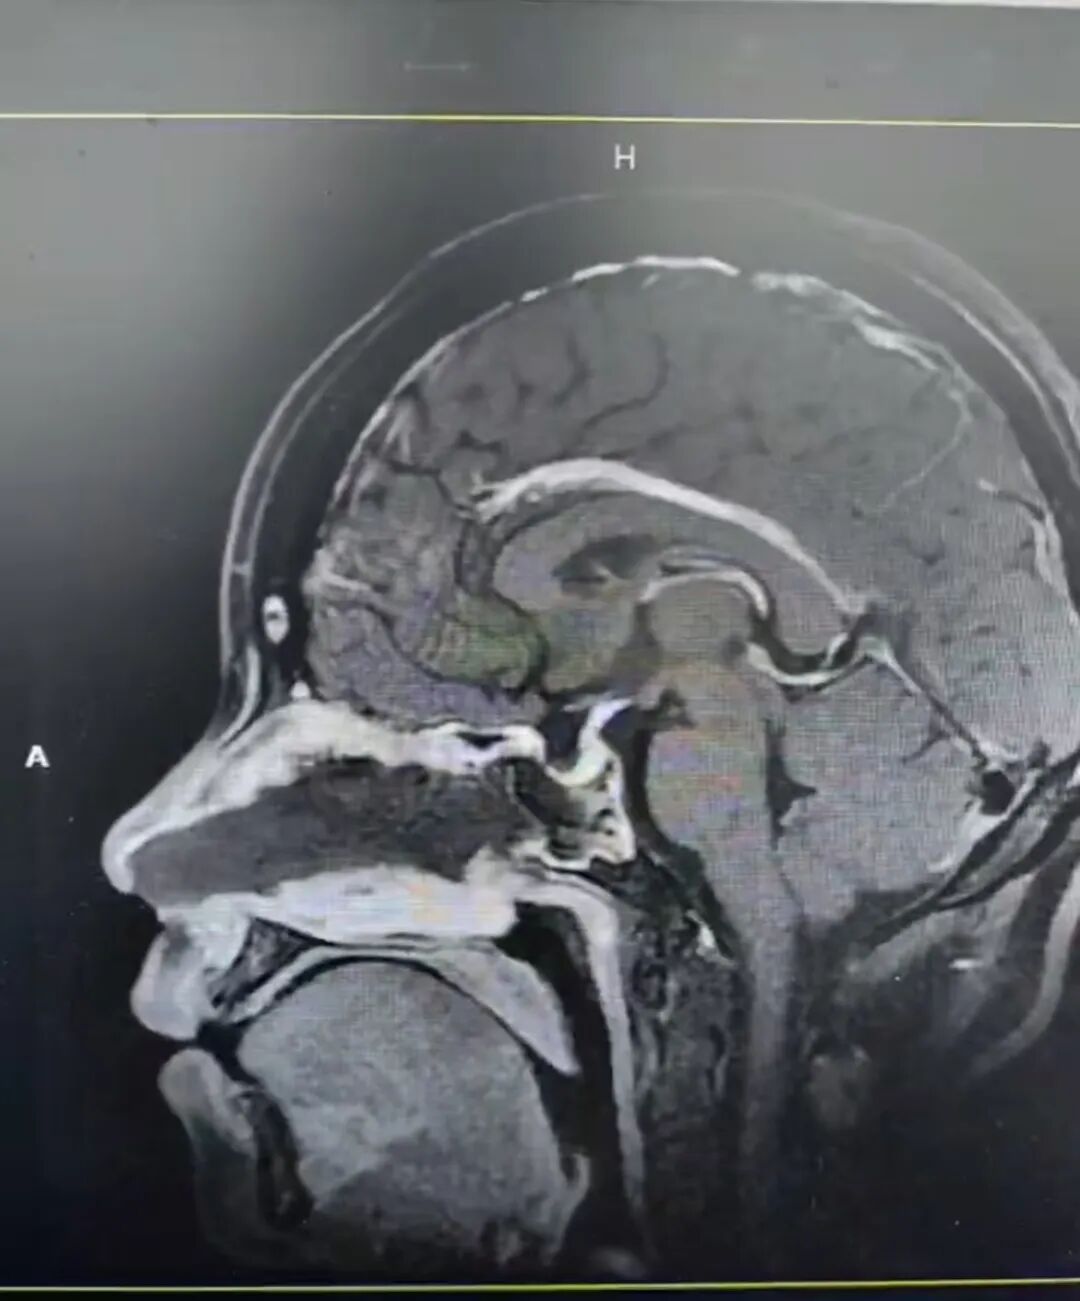

手術(shù)前后影像

26歲的患者小麗(化名)因“月經(jīng)不調(diào)3年,發(fā)現(xiàn)泌乳素升高10天”就診于冊亨縣人民醫(yī)院。經(jīng)診斷,醫(yī)生考慮

泌乳素瘤

可能性大。

在內(nèi)鏡下經(jīng)鼻單鼻孔這一微創(chuàng)路徑為患者實施手術(shù)。

這一術(shù)式猶如在針尖上跳舞,對醫(yī)生的操作要求很高。醫(yī)生需要在極其狹小的鼻腔空間內(nèi)精準(zhǔn)操作,如同在荊棘叢中開辟出一條通往病灶的“絲綢之路”,小心翼翼地避開錯綜復(fù)雜的神經(jīng)、血管,最終直達(dá)病灶,將腫瘤成功切除。

手術(shù)當(dāng)天,惠州三院神經(jīng)外科副主任文世宏主任醫(yī)師作為主刀醫(yī)生,攜手醫(yī)療團隊,與冊亨縣人民醫(yī)院的醫(yī)護人員緊密合作,憑借著高超的技術(shù)與默契的配合,順利完成了該手術(shù)。